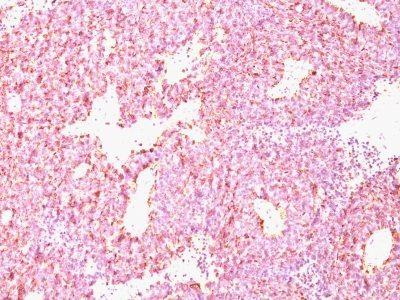

Chromogranin A is present in neuroendocrine cells throughout the body, including the neuroendocrine cells of the large and small intestine, adrenal medulla and pancreatic islets. It is an excellent marker for carcinoid tumors, pheochromocytomas, paragangliomas, and other neuroendocrine tumors. Co-expression of chromogranin A and neuron specific enolase (NSE) is common in neuroendocrine neoplasms. Reportedly, co-expression of certain keratins and chromogranin indicates neuroendocrine lineage. The presence of strong anti-chromogranin staining and absence of anti-keratin staining should raise the possibility of paraganglioma. The co-expression of chromogranin and NSE is typical of neuroendocrine neoplasms. Most pituitary adenomas and prolactinomas readily express chromogranin.Primary antibodies are available purified, or with a selection of fluorescent CF® Dyes and other labels. CF® Dyes offer exceptional brightness and photostability. Note: Conjugates of blue fluorescent dyes like CF®405S and CF®405M are not recommended for detecting low abundance targets, because blue dyes have lower fluorescence and can give higher non-specific background than other dye colors.

Positive Control

PC12 cells. Adrenal gland, bowel, thyroid, pancreas, or pheochromocytoma.

Neuroendocrine cells

Tumor expression

Neuroendocrine cancer|Pituitary cancer